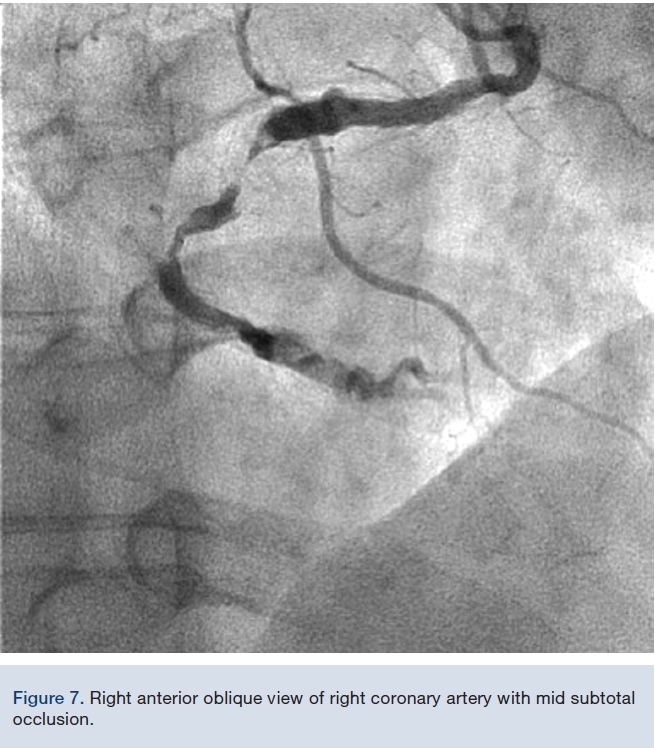

Given the tortuosity and calcification, very good catheter support was needed for PCI. An 8 French (Fr), 45 cm sheath was inserted into the femoral artery and an 8 Fr multipurpose guide catheter was chosen. After deep intubation of the RCA with the guide catheter, a Balance Middleweight guide wire (BMW) (Medtronic) was used to cross the lesion; however, just as the BMW crossed, the guide catheter prolapsed back into the aorta. At this point, an 8 Fr GuideLiner was inserted into the guide catheter with a 5.5 Fr GuideLiner inserted into it (outside the patient) over a BMW (Figures 1-2). This system was advanced into the RCA with the guide catheter deeply seated. The 8 Fr GuideLiner tip was advanced to the mid RCA and the 5.5 Fr GuideLiner tip reached mid vessel. With this support system, both stenoses were predilated with a 2.5 x 15 mm non-compliant balloon. First, a 3.5 x 12 mm Xience stent (Abbott Vascular) was placed in the distal coronary lesion, which required pushing of the 5.5 Fr GuideLiner further into the distal vessel, past the first lesion (Figure 4). Next, a 4.0 x 28 mm Xience stent was advanced to the distal tip of the 5.5 Fr GuideLiner and it was “de-sheathed” by pulling the GuideLiner back. With a good final result, the patient was discharged home the following day in good condition and remained angina free.